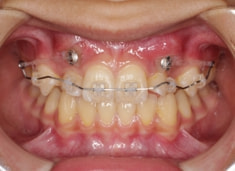

治療開始時

FX(フェイシャルアキシス)は85度なので東洋人の平均値に近く、下顎が前方に過剰成長するリスクは強くはありません。

しかしやはり上顎は劣成長で、下顎が優位な状態ではあります。

上下顎のギャップはありますが、顔面自体の幅径は良好な値を示していますので、スペース不足は拡大することによって解決できポテンシャルはあると考えられます。

左右の非対称もさほど強くありません。

骨年齢は実年齢よりも低めなので、今後下顎の旺盛な成長が見込まれます。

検査時のレントゲン分析では、上下顎の関係は、上顎の劣成長があり下顎前突傾向という値がでておりましたが、前歯ジャンプ後はフェイスマスクの効果もあり、上下顎の関係は正常化しています。

上顎が若干優位になっていますので、今後の下顎の成長のための貯金になっているくらいです。